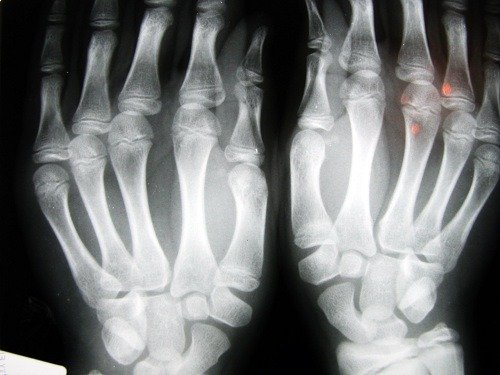

Osteoporos är en bensjukdom som orsakar en minskning av benmassans densitet. Denna sjukdom kännetecknas av porösa ben. Genom att storleken på de inre cellerna i benen förstoras, blir de spröda och går lättare av.

Denna sjukdom är tyst eftersom den ofta pågår obemärkt tills den orsakar någon skada på benet.

Frakturer förekommer ofta i handlederna och även i höfterna. Det senare är den allvarligaste frakturen eftersom den kräver omedelbart kirurgiskt ingrepp och innebär allvarliga konsekvenser för patientens hälsa.